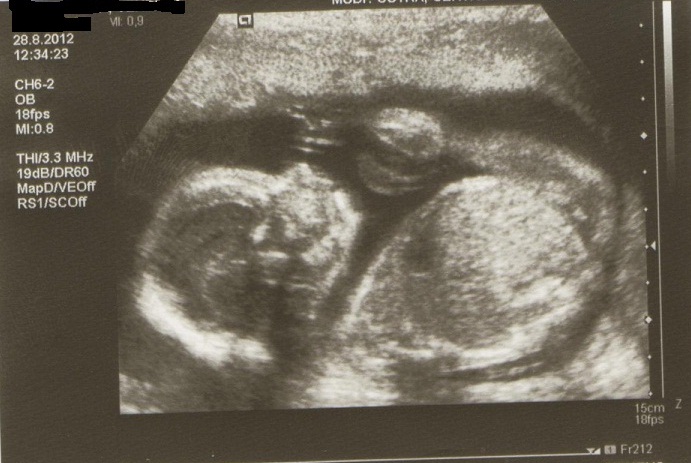

Holky přidávám fotečky naší malinké z minulého týdnu z velkého utz. Dostali jsme tři na dvou je skoro celá a na jedné je záběr na pusinku.